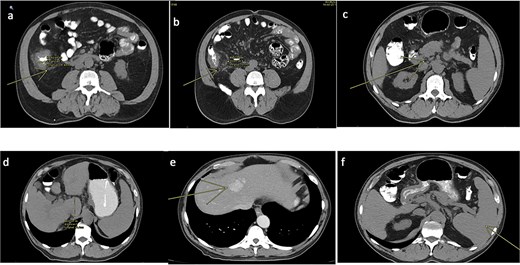

A follow-up abdominal CT scan revealed post-surgical changes consistent with a right hemicolectomy and ileotransverse anastomosis, along with a moderate amount of free intraperitoneal fluid (Fig. 2).

Abdominal CT scan (non-contrast). (a) Anastomotic staples and drain trajectory. (b) Presence of free intraperitoneal fluid.